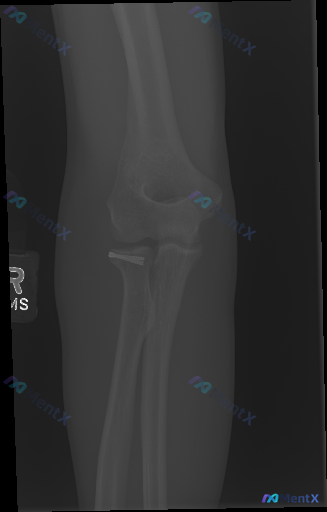

整理了一张右侧肘关节侧位X光片的资料,先和大家同步下影像里看到的客观情况: - 桡骨头颈部区域有一枚小“Y”/钩状的金属内固定物 - 除该区域的骨改建痕迹外,其余肱骨远端、尺骨近端、桡骨干皮质连续,未见明确新鲜骨折线/脱位 - 肱前嵴线穿过肱骨小头中1/3,关节对位、间隙看起来还行 - 肘关节周围(...

整理到一张左侧肘关节的侧位X光片,先放核心影像所见,大家来聊聊思路: - 标注L,左侧肘关节侧位 - 肱尺、肱桡关节对位基本可,无明显脱位/半脱位 - 关键:桡骨头颈部可见高密度金属内固定物(微型螺钉类) - 前/后脂肪垫征阴性,无明显“帆船征” - 整体骨密度无弥漫异常,关节面尚平整,无明显急性骨...